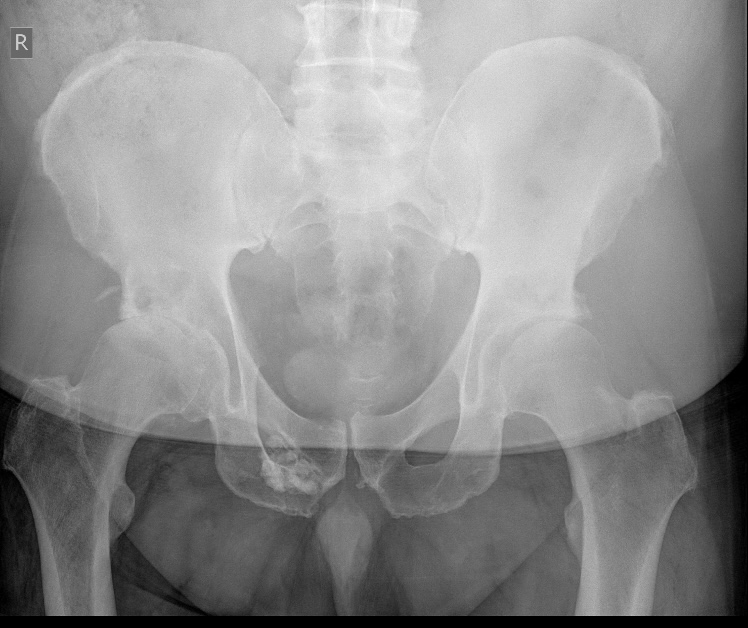

I went to see the doctor on Thursday when he looked at the image and took his glasses off slowly and asked me a question and id say for the first time in 20 years he looked concerned, are you ok Paul, mate how are you living, can I ask how are ya getting dressed, walking, etc mmm short stories he has put it down as critical and urgent attention needed to be sent the report into hospital see what happens.